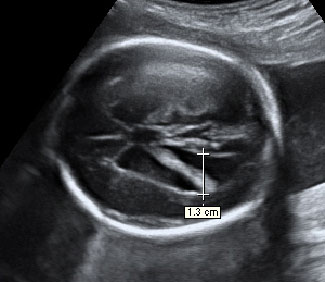

En la ecografía podemos ver una hernia intestinal (u onfalocele), lo que significa que parte del intestino del feto está fuera del abdomen. Observamos la sección transversal del abdomen fetal. A la izquierda, contenido intestinal (entre marcas de medición) herniado fuera del abdomen, debido a un defecto en la inserción del cordón umbilical, que se marca en la imagen con una estrella (*).

Onfalocele o intestino del feto fuera del abdomen